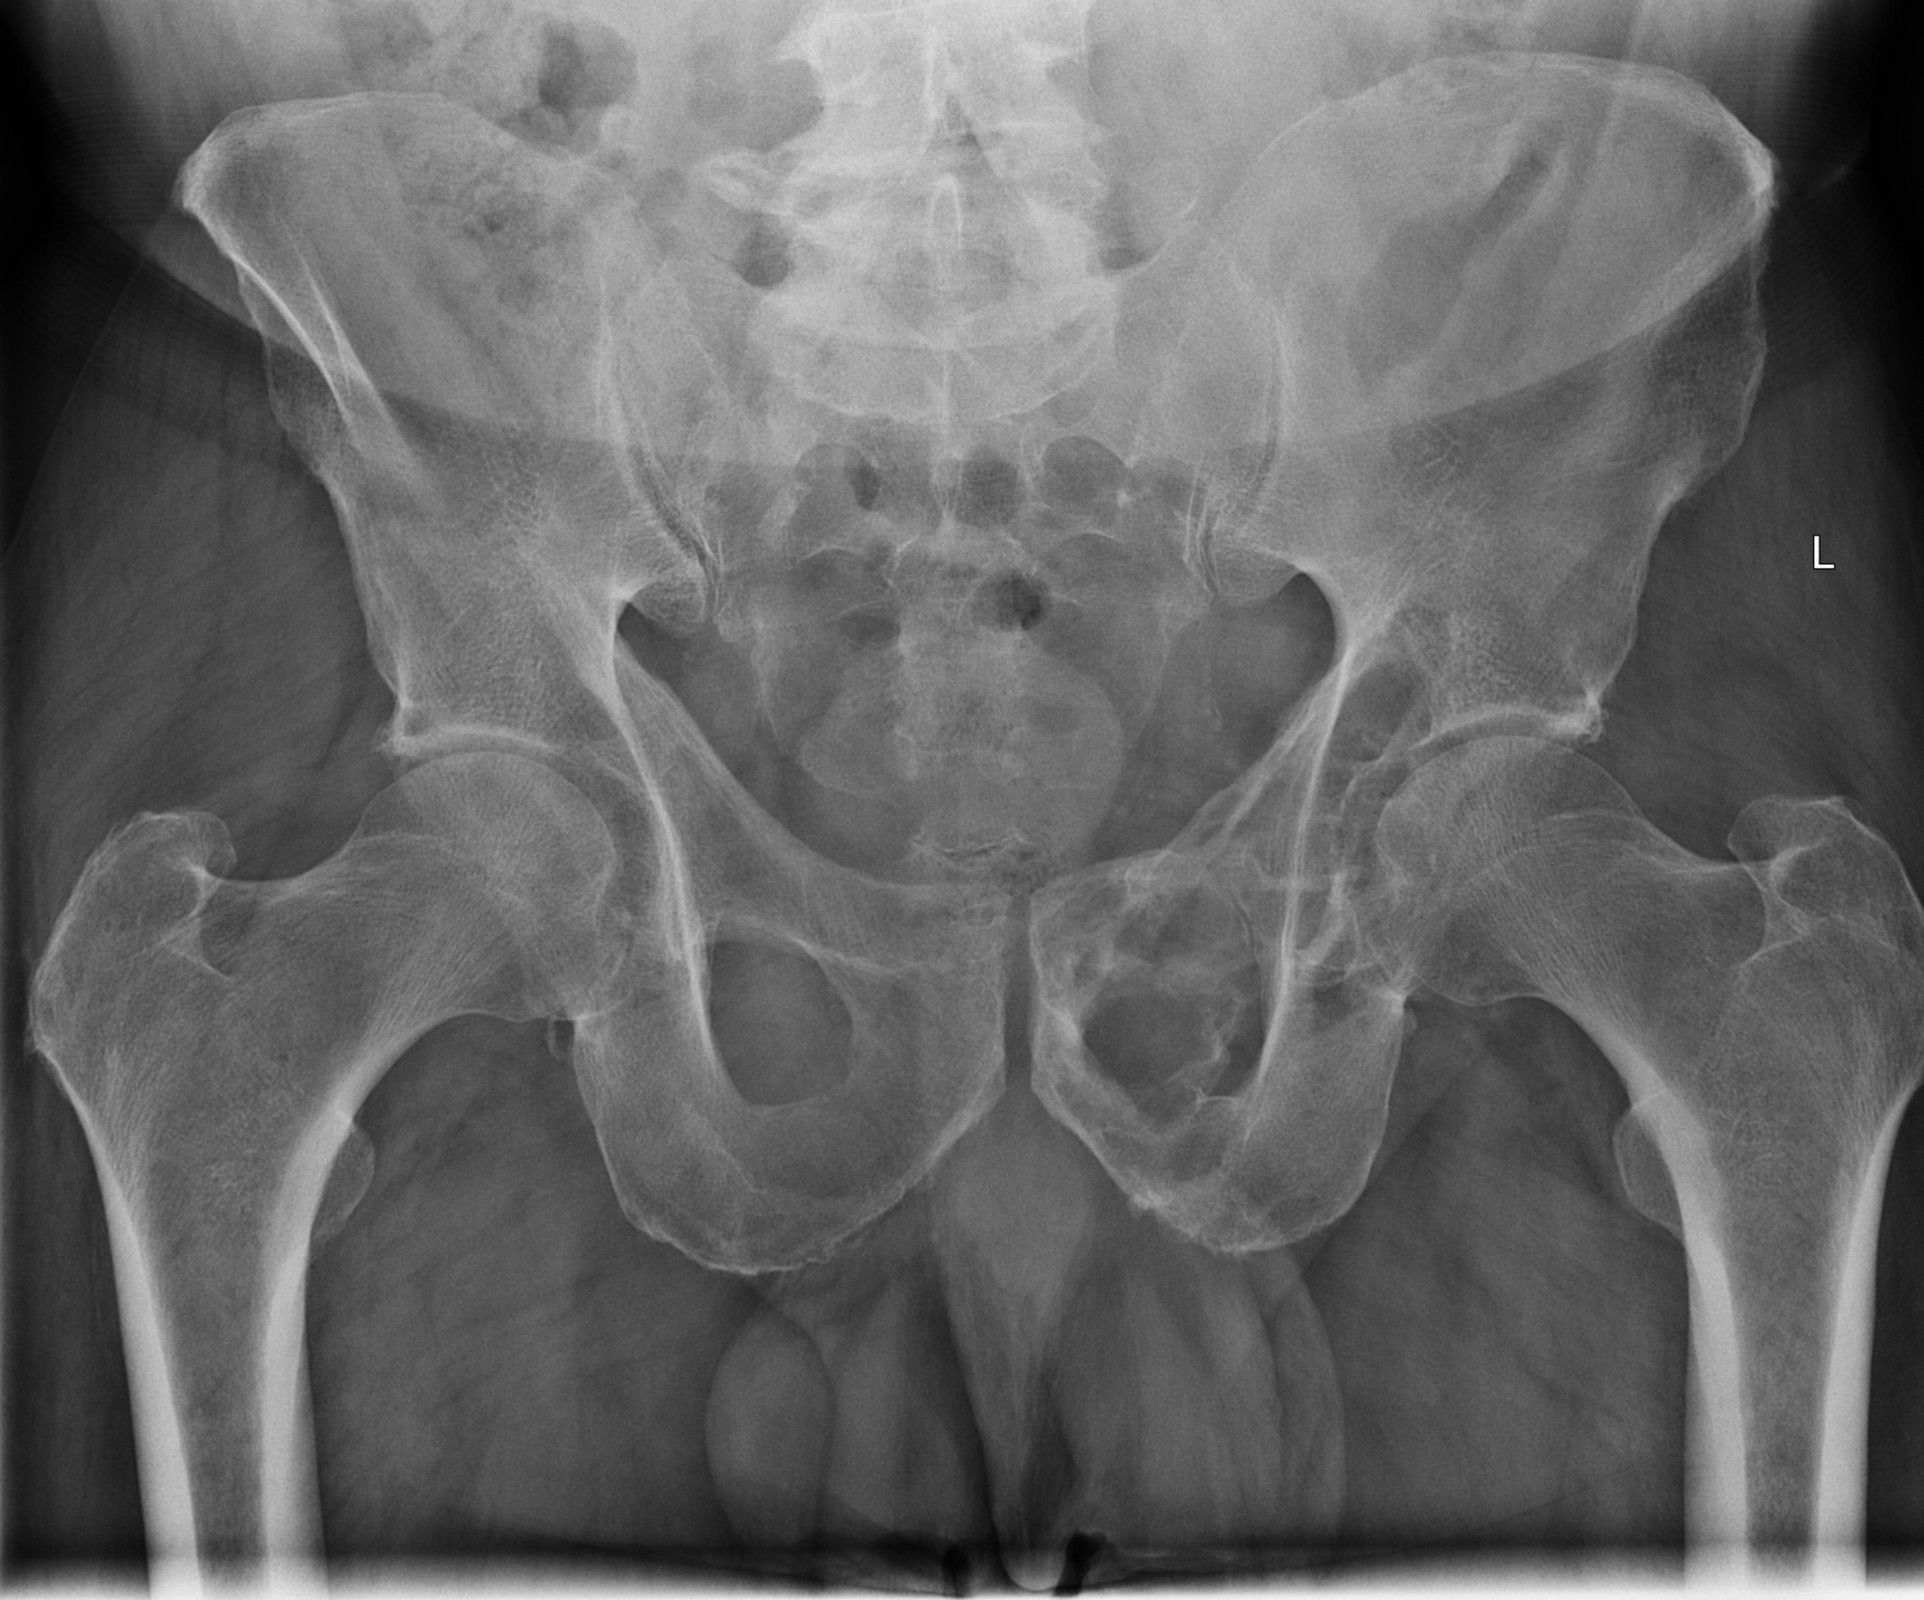

Röntgenfall des Monats